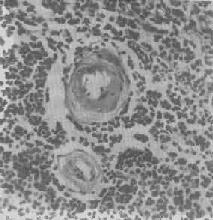

脾中央动脉玻璃样变

图1-20 脾中央动脉玻璃样变

中央动脉管壁明显增厚,呈玻璃样均质状,管腔变窄

2.血管壁玻璃样变:这种改变常见于高血压病时的肾、脑、脾及视网膜的细动脉。此时,可能是由于细动脉的持续性痉挛,使内膜通透性增高,血浆蛋白得以渗入内膜,在内皮细胞下凝固成无结构的均匀红染物质。此外,内膜下的基底膜样物质增多。这些改变使细动脉的管壁增厚、变硬,管腔变狭,甚至闭塞(图1-20),此即细动脉硬化症(arteri-olosclerosis),可引起肾及脑的缺血。